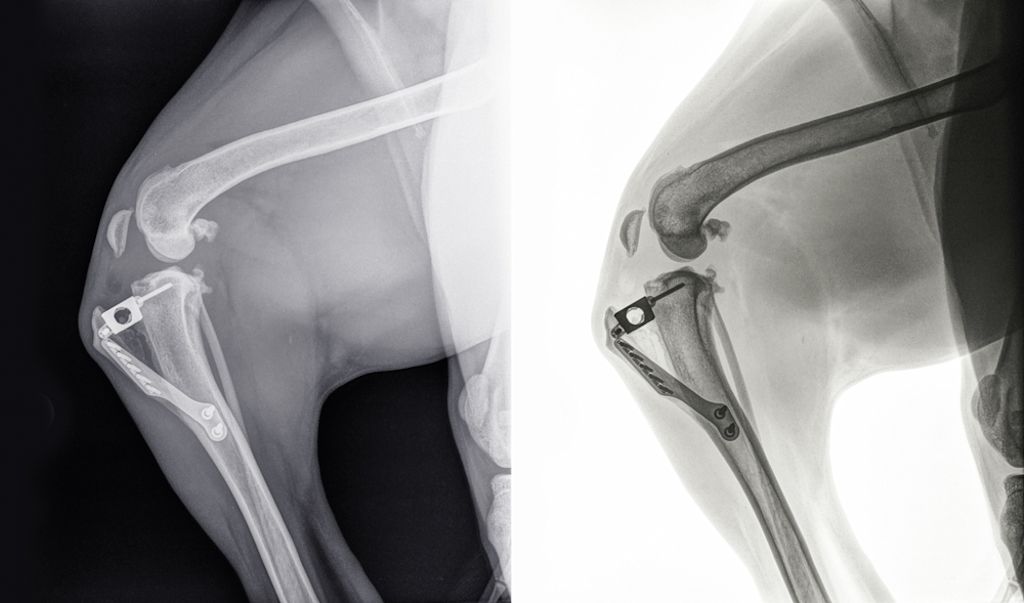

● Osteotomía niveladora del plato tibial (TPLO): esta técnica consiste en modificar la biomecánica de la rodilla mediante el corte y la rotación del plato tibial para que la tibia no se deslice hacia adelante. Es una de las opciones más populares para perros grandes y activos.

● Avance de la tuberosidad tibial (TTA): en esta cirugía, se adelanta la tuberosidad tibial para cambiar las presiones en la rodilla y estabilizar la articulación. También se utiliza en perros de gran tamaño.